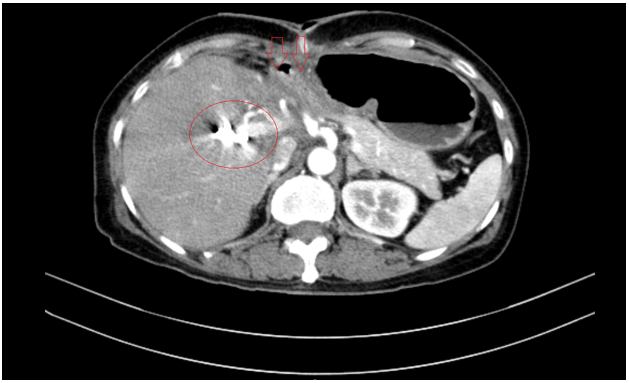

Tháng 01/2025 Bệnh nhân ở nhà xuất hiện mỏi, vàng da, ngứa kèm sốt kéo dài một tháng, đợt này đau bụng mạn sườn phải, kèm vàng da tăng dần, đi khám ở bệnh viện tuyến dưới, siêu âm có sỏi đường mật gan trái kích thước 22x41mm. Bệnh nhân được chuyển đến bệnh viện Bạch Mai và được chụp CT ổ bụng phát hiện, kết quả:  Gan có kích thước bình thường, bờ đều,  nhu mô hạ phân thuỳ IV có ổ tổn thương dạng dịch kích thước 40x53mm, trong có sỏi lớn đường kính 35mm.

Hình 1. Hình ảnh sỏi đường mật tạo ổ áp xe gan - đường mật gan trái (vòng tròn màu đỏ). Giãn nhẹ đường mật trong gan hai bên. Dày thành nhẹ ngã ba đường mật trên phim chụp cắt lớp vi tính.